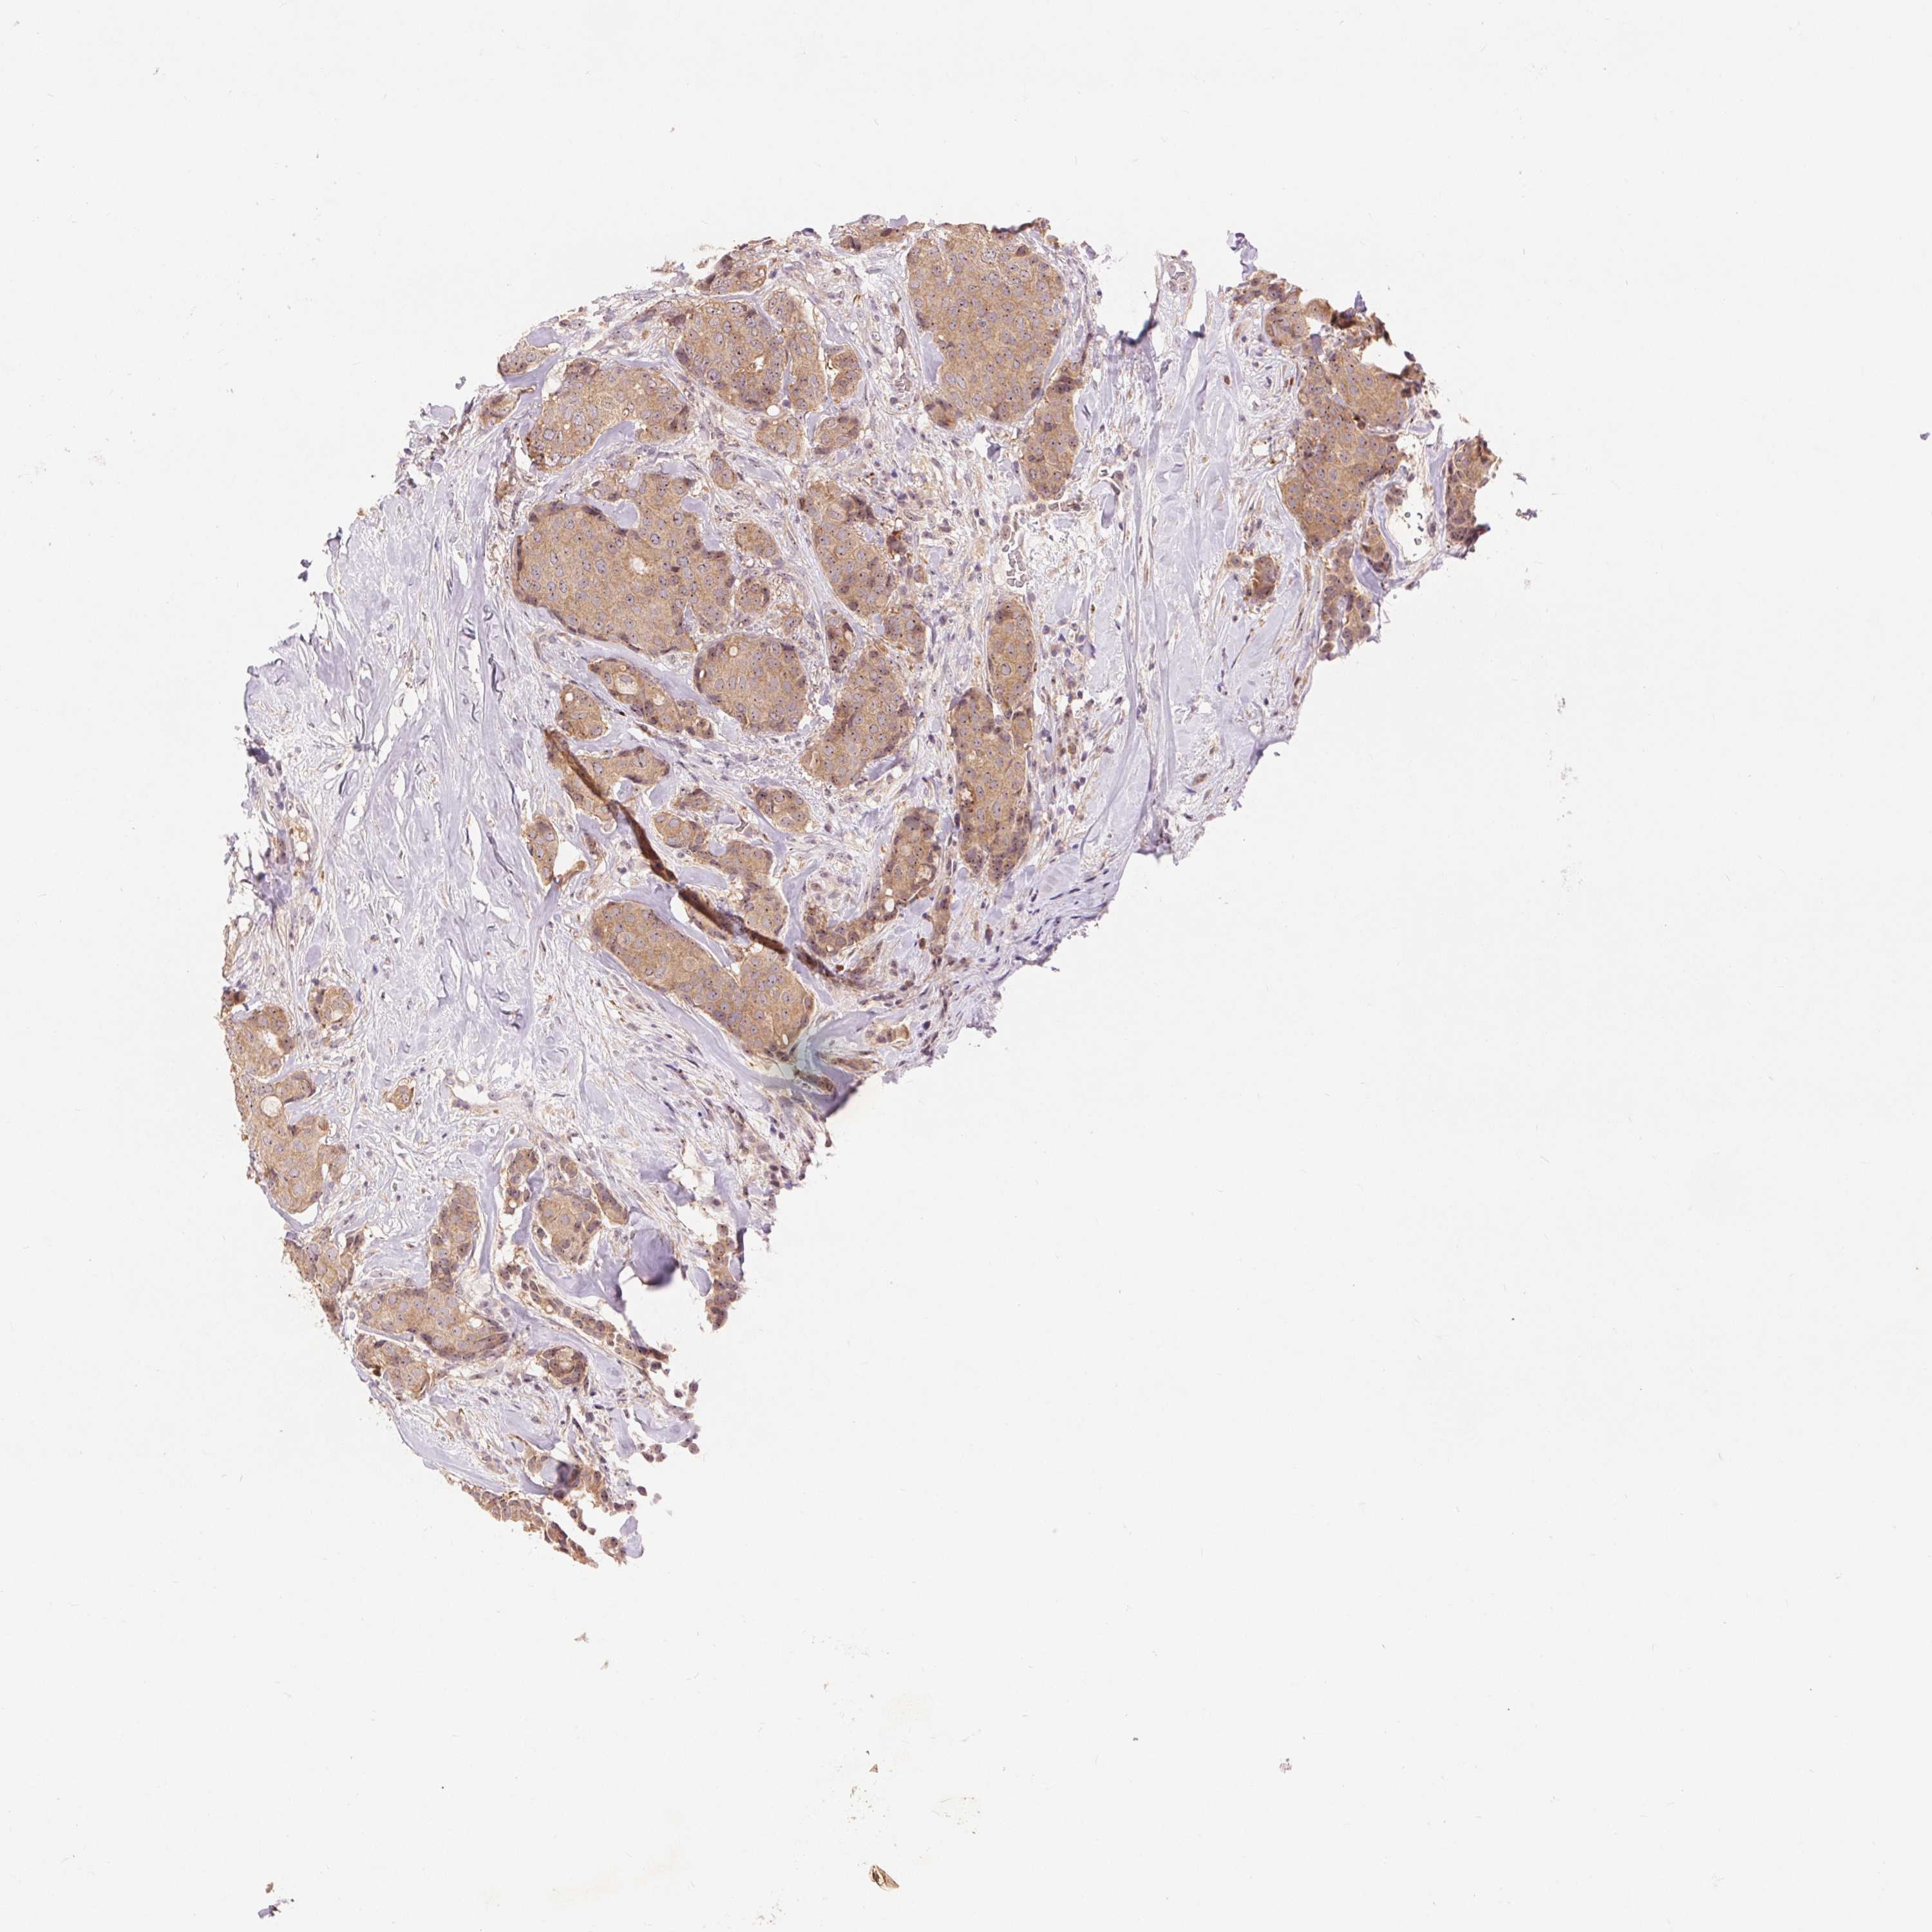

CANCER BREAST CANCER Show tissue menu

BRCA TCGA BRCA VALIDATION PROTEIN EXPRESSION